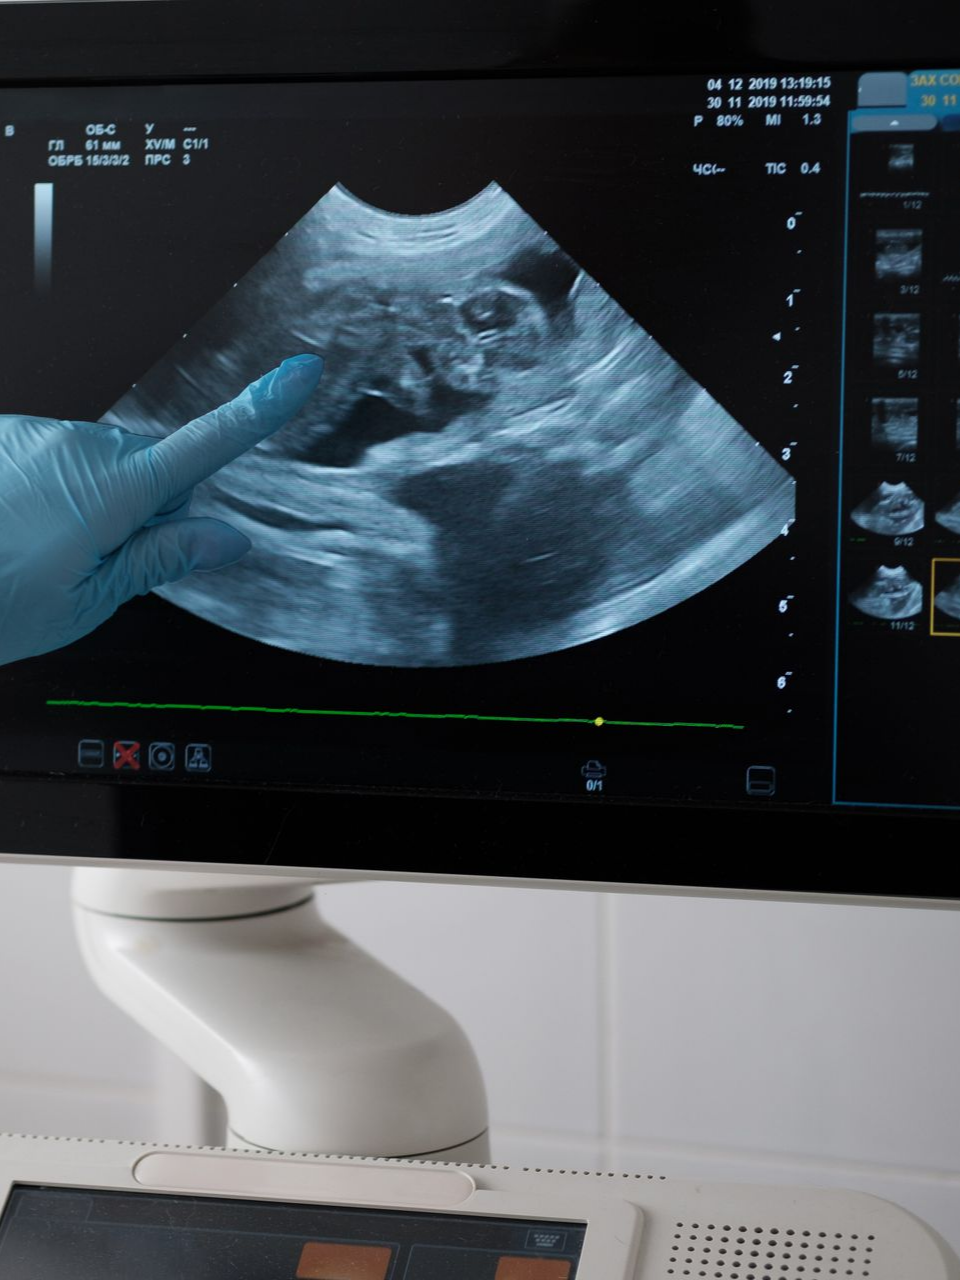

Enfin, les

échographies fœtales (T1, T2, T3) sont essentielles pour le suivi de grossesse, assurant une surveillance précise du développement du bébé.